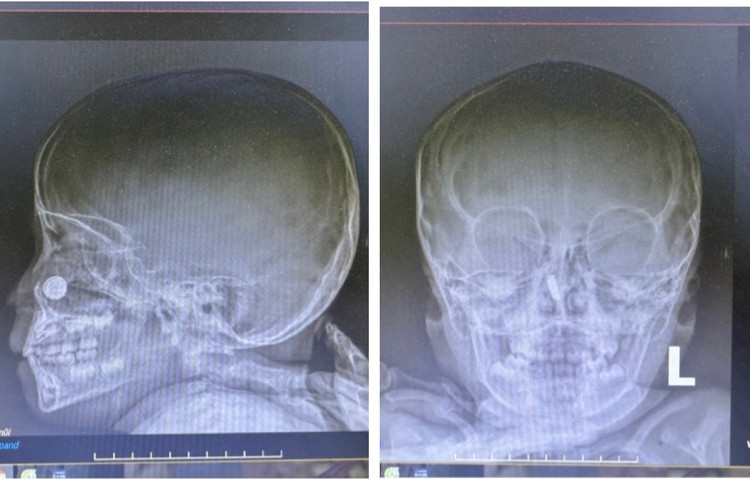

Sau khi thăm khám và cho bệnh nhi dùng 02 loại kháng sinh phối hợp chống viêm, các bác sỹ Khoa Liên Chuyên khoa đã chỉ định cho bệnh nhi chụp X-quang sọ não mặt thẳng/nghiêng và nhận thấy hình ảnh cản quang vị trí hốc mũi phải.

Các bác sỹ nhận định đây là trường hợp có dị vật nguy hiểm trong mũi cần phải nhanh chóng lấy ra nên đã nội soi và gắp ra dị vật là viên pin cúc có đường kính khoảng 01cm, pin đã bị oxy hoá đen vỏ. Rửa sạch hốc mũi trẻ kiểm tra thấy viên pin cúc đã ăn mòn cuốn mũi và vách ngăn mũi.

| Kết quả chụp X-quang sọ não mặt thẳng/nghiêng cho thấy có dị vật ở mũi bệnh nhi - Ảnh BVCC |